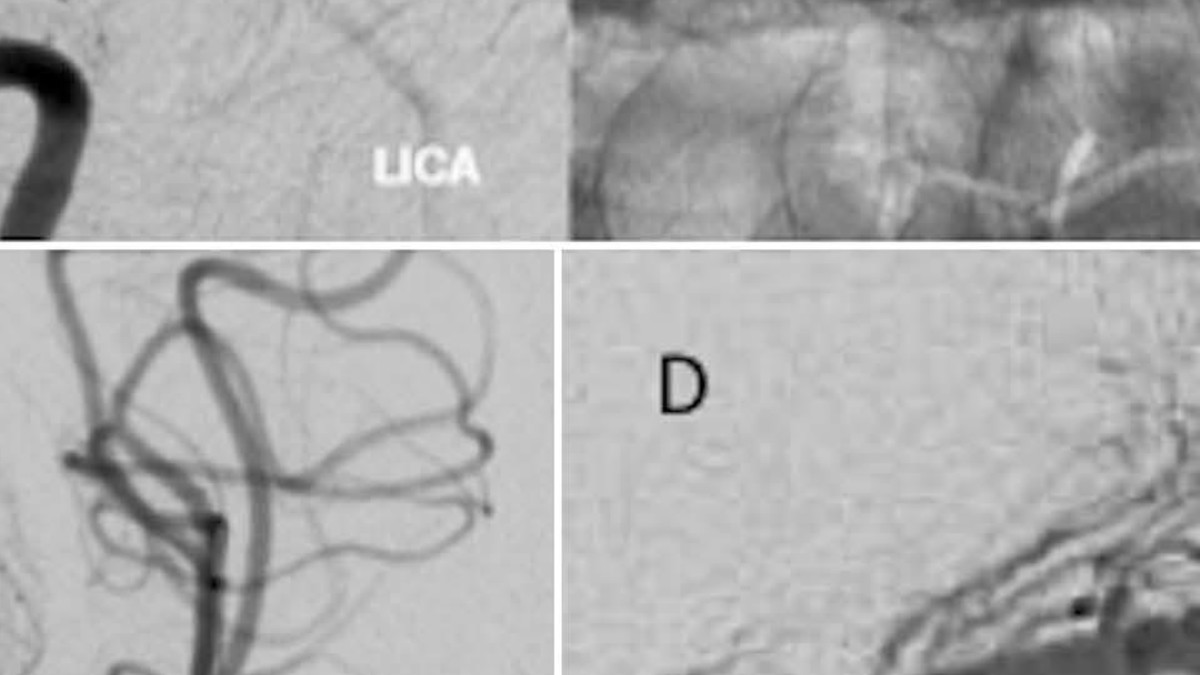

Στενώσεις ενδοκράνιων αγγείων – Ενδείξεις αντιμετώπισης

Ημερίδα – Επιστημονική εκδήλωση Ελληνικής Αγγειολογικής Εταιρείας

«Φθινοπωρινές ημέρες Αγγειακών Παθήσεων»

Ίσθμια Κορινθίας, Αθήνα 2016

• Στενώσεις ενδοκράνιων αγγείων – Ενδείξεις αντιμετώπισης